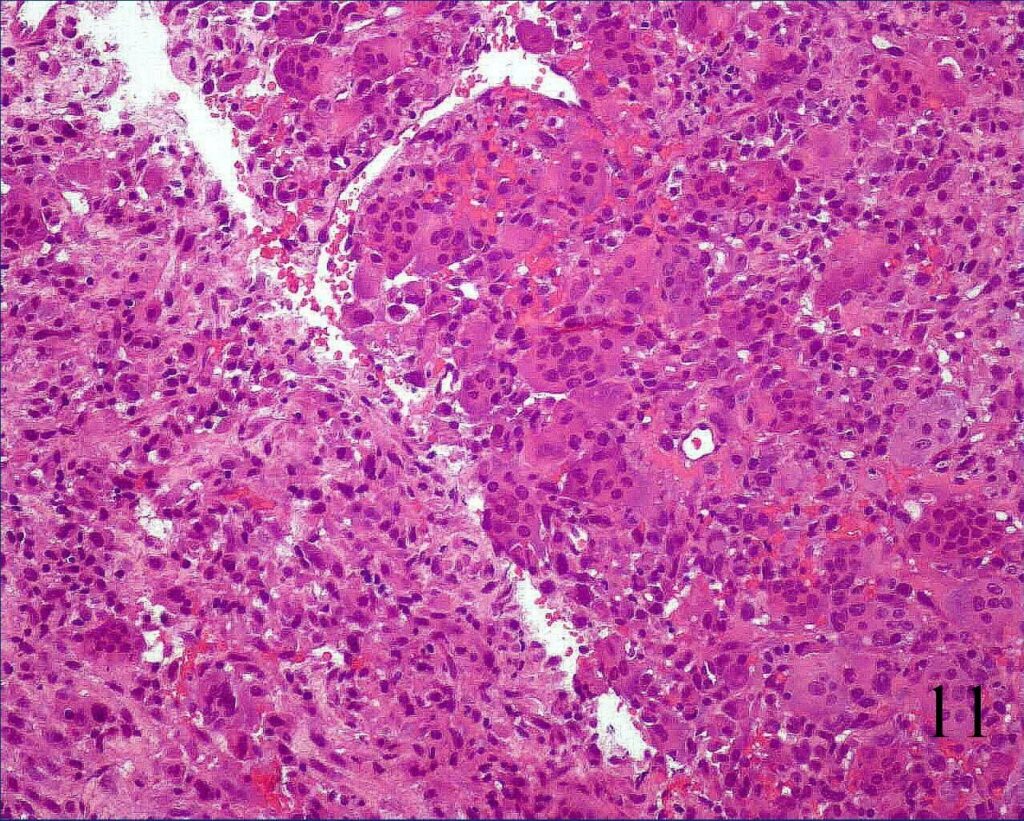

Microscopic

- Giant cells evenly and widely dispersed throughout the tumor admixed with mononuclear cells. There is no matrix.

- The nuclei of the giant cells and nuclei of the mononuclear background cells are similar (Fig. 11)

Fig. 11 Microscopic: Low power magnification of lesion composed multiple of multiple multinucleated giant cells in mononuclear background cells.